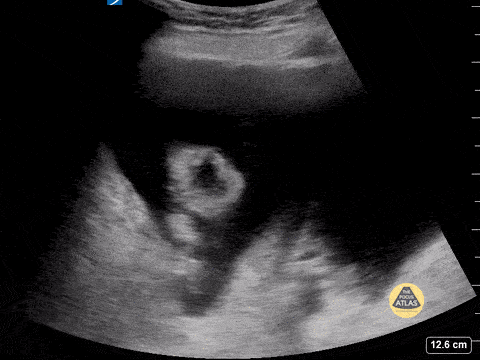

Ascites with floating bowel and questionable to-and-fro peristalsis. Contributor: Peter Gutierrez, MD, FAAP, Emory University School of Medicine/Children's Healthcare of Atlanta, @pocuspete